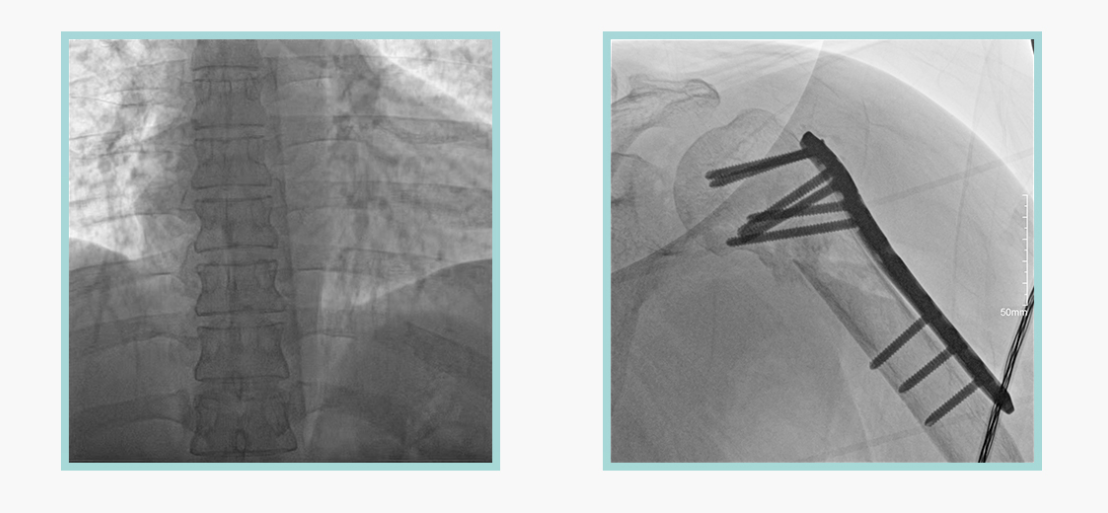

作为全球X线机的主要参与者,尊龙凯时人生就是博科技在数字化X线产品线实现全线动态化之外,在移动C臂X光机产品线领域推出全新平板移动C臂产品:悦画。随着国家“千县工程”提升基层医疗卫生服务能力,外科对于手术介入引导设备的需求剧增。对于一台优秀的移动C臂X线机而言,如何保证最优质影像的同时,最大程度降低X线的辐射剂量,并在满足临床手术引导/定位的同时,最大程度的保护临床手术的医务人员,是悦画最为关切的问题。

此外,骨科手术时间平均时长约为45分钟左右时间,长期的X线透视或摄影曝光剂量将对临床手术与操作医务工作者造成难以评估的健康风险,悦画通过支持摄影曝光参数的自主调节,可以保证在最低剂量水平下输出满足临床手术定位与引导所需要的影像质量,相较于市面上的固定曝光参数配置移动C臂,自主参数调节设计的曝光功能设计,可以大幅减少医务工作者的X线辐射剂量。

不仅如此,悦画在产品的剂量安全管理上,还支持DAP剂量实时显示与统计功能。为了减少误操作的X射线曝光,悦画具有X射线锁定保护功能,在摄影曝光停止后立即进行X射线曝光锁定,解锁后才能支持继续曝光,减少以往临床过程中医务工作者因为误操作所导致的额外X射线辐射。